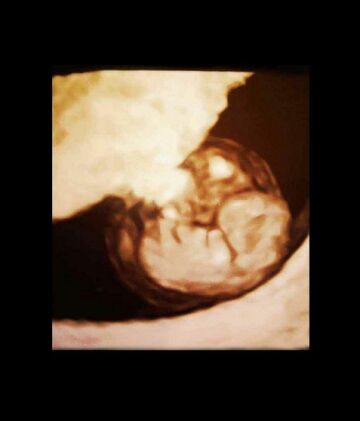

其次则是超音波检查,区分子宫内妊娠、葡萄胎、子宫外孕等状况,以及是否并发子宫或卵巢肿瘤,若能清楚看到胎心搏动,通常表示尚无大碍。